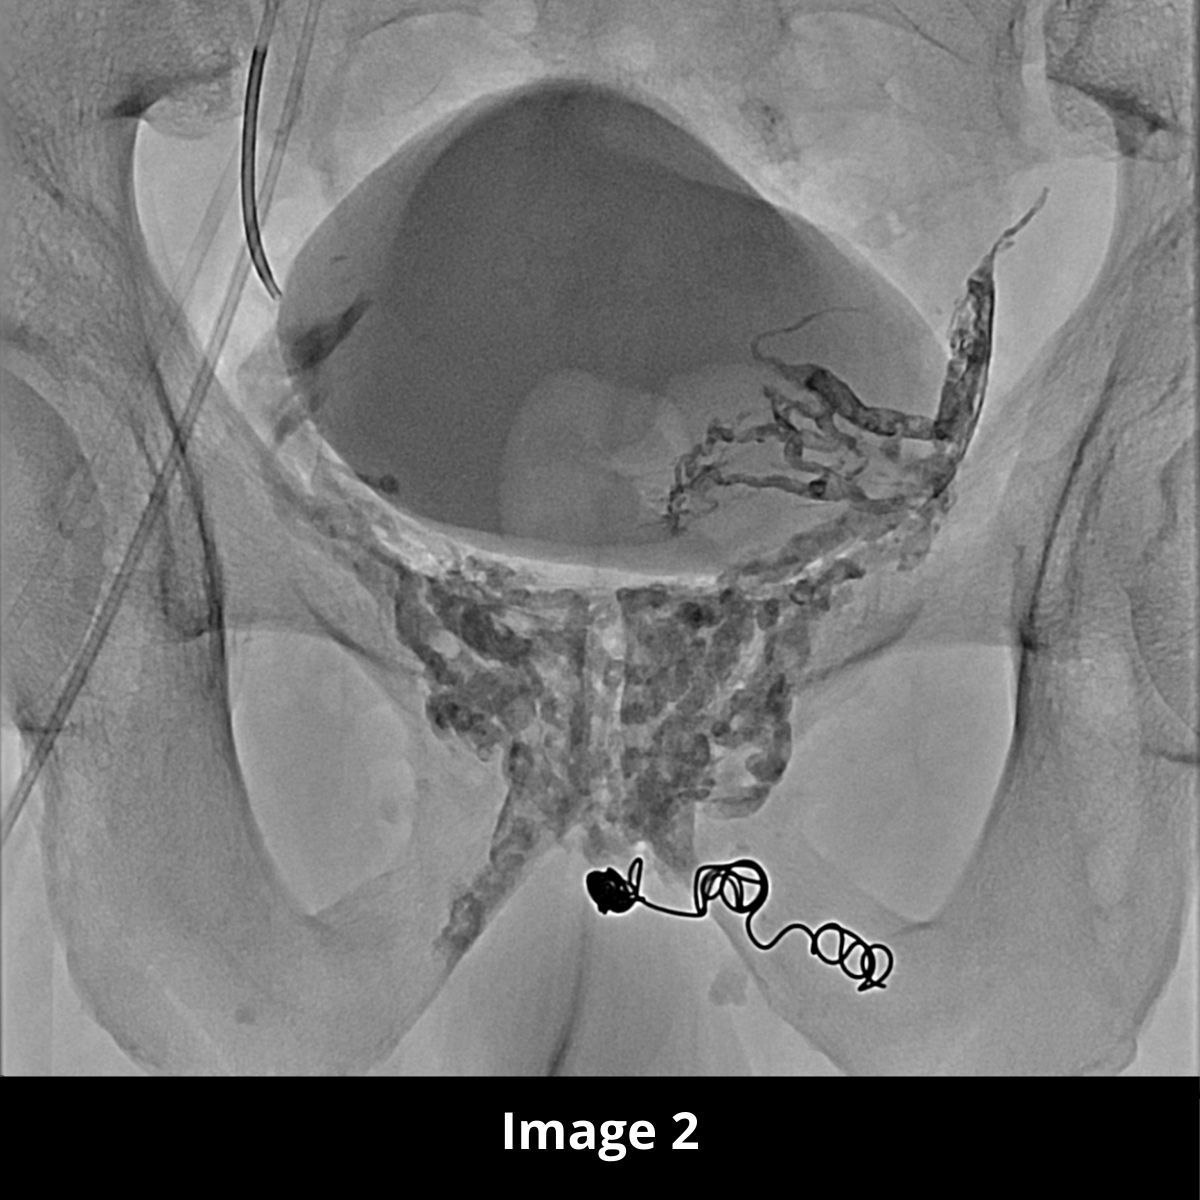

Nous procédons donc à une embolisation par agent liquide (lave) avec un résultat optimal (image 2 en graphie et image 3 en CBCT reconstruction coronale).